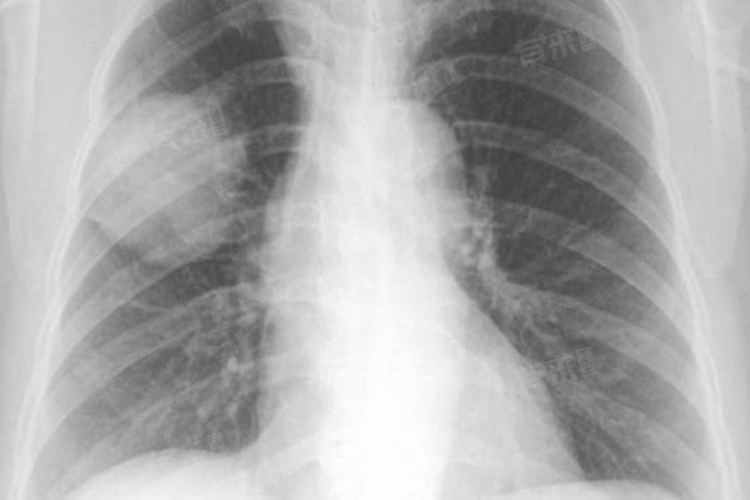

右肺中叶条索是在医学影像学检查(如胸部X线、CT等)中观察到的一种表现,具体指的是在右肺中叶区域出现条索状的阴影或高密度影。这种影像学改变通常反映了肺部过去存在的炎症、感染或其他病变,经过治疗或自然愈合后遗留下的纤维化病灶。

- 右肺中叶条索的形成原因多种多样,包括肺脓肿、肺炎、陈旧性肺结核、原发性肺结核、支气管扩张等。这些疾病在发病过程中,肺组织会受到不同程度的损伤,随后在修复过程中,纤维结缔组织会替代受损的肺组织,从而在影像学上形成条索状的改变。

右 肺中叶条索的诊断还需要结合患者的临床症状、病史以及进一步的影像学和实验室检查。所以,发现右肺中叶条索时,患者应及时就医并告知医生自己的详细情况,以便医生做出准确的诊断和制定合适的治疗方案。